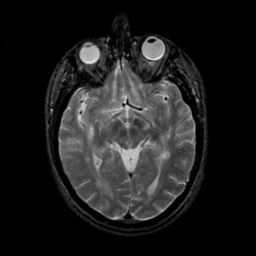

MR Study #9, April 14, 1991 -- Slice #22

[Home][Help][Clinical][Tour 1][Tour 2] Slice 22